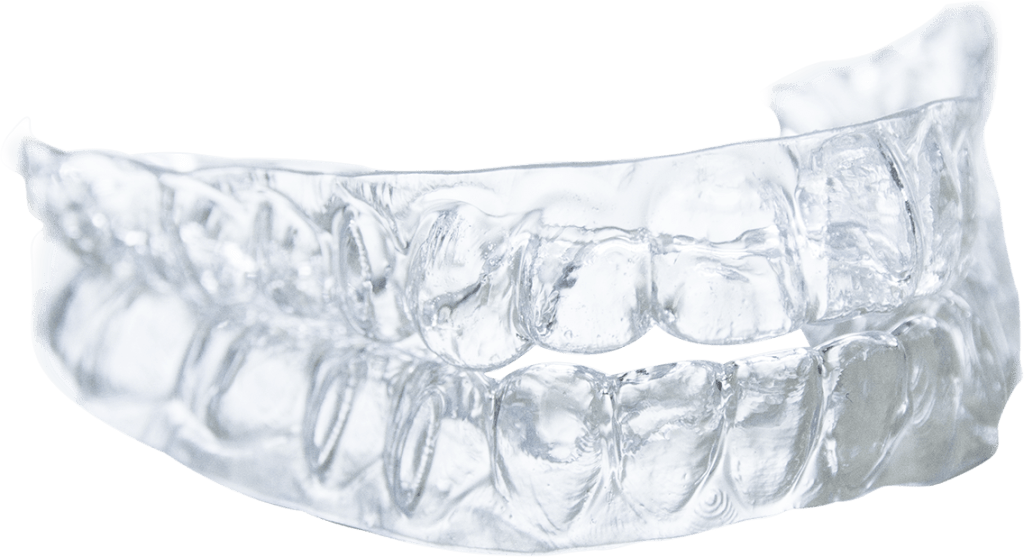

So I spend a lot of time convincing my patient that the brux to hopefully motivate them to wear a night time occlusal shield. I do not use occlusal shields on growing dentition. I do not use the traditional hard acrylic occlusal shields which can be more than 2 or 3 mm thick and used on one arch only – either top or bottom. Over the years there has been follow up studies that shows that the 5 year retention rate of hard occlusal splints is about 3%. Dismal really. Therefore it is true that hard acrylic occlusal splint last a long time because they spend more time in the drawer than in the mouth

On the other hand soft splints made with thermoplastics when made thinner, 1 to 2 mm, has a greater than 90 % retention rate, if not close to 100%. This I state as an anecdotal evidence only as I am quoting my own unofficial clinical data. The reason I can be quite confidence of my assertion is because the soft splints are also the same material I use as my post orthodontic treatment retainers. For over 25 years I have been practicing orthodontics and for most of the cases in that 25 years I have used the thermoplastics as retainers